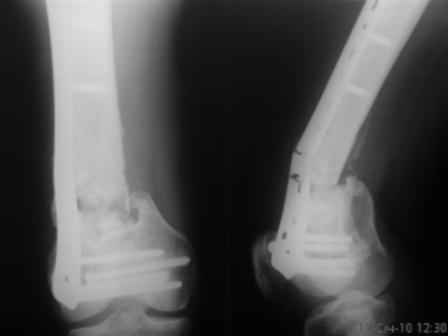

Уважаемые коллеги! Просьба поделиться соображениями в выборе дальнейшей тактики лечения. Больной, 30 лет, высокоэнергетическая травма 6 мес назад (базальный перелом шейки бедра + перелом дистального метаэпифиза бедра на той же ноге по типу 33-С2). Практически сразу же был произведен МОС шейки системой DHS (Synthes), через две недели - МОС дист.отдела бедра системой LISS (Synthes)плюс костная пластика с крыла подзвдошной кости. На сегодняшний день наступил перелом пластины, укорочение бедра 2 см. Перелом шейки клинически и рентгенологически сросся. Больной астеничен, немного анемичен. Рентгенограммы прилагаются.С уважением, Тарас Рокита, гор.больница 7, Киев